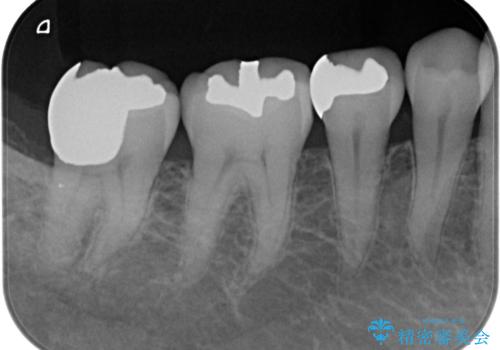

- 右下7 : ゴールドアンレー / 110,000円費用は治療当時の料金となります

歯肉を整理し、今後同じことを繰り返さないよう精度の良いゴールドアンレーで修復処置を行いました。